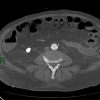

Nhồi máu ruột

» Thông tin: Nam giới – 85 tuổi.

» Lâm sàng: Đau bụng cấp.

# Dày thành ruột – Khí thành ruột – Khí tĩnh mạch mạc treo.